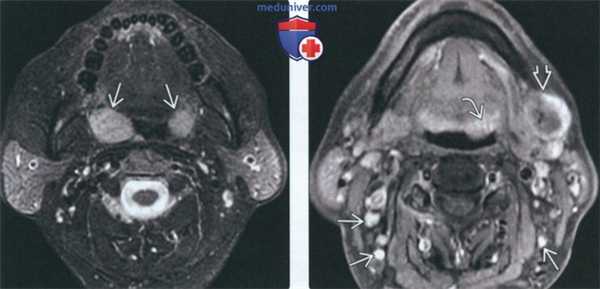

(Слева) На аксиальной МРТ (Т2 ВИ FS) определяется хорошо отграниченная НХЛ миндалины справа. Небольшой размер левой миндалины является нормой для взрослых людей, т. к. лимфоидная ткань подвергается возрастной инволюции. Плоскоклеточный рак миндалины и доброкачественная смешанная опухоль могут выглядеть идентично, диагноз НХЛ подтверждается только при помощи биопсии.

(Справа) На аксиальной МРТ (Т1 ВИ С+) у этого же пациента определяется однородное контрастирование НХЛ миндалины. При инфекционном поражении миндалин наблюдается «исчерченная» картина контрастного усиления, абсцесс миндалины характеризуется центральным некрозом.

(Слева) На аксиальной МРТ (Т2 ВИ FS) определяется мультифокальная НХЛ обеих небных миндалин. Четкие края позволяют предположить, что опухоль ограничена капсулой миндалин.

(Справа) На аксиальной МРТ (Т1 ВИ FS) у этого же пациента визуализируется дополнительный участок поражения лимфоидной ткани НХЛ в основании языка слева, а также крупный некротический лимфоузел IB уровня. Присутствуют множественные мелкие шейные лимфоузлы, однако лишь оценка метаболической активности с помощью, например, ПЭТ/КТ, позволяет выявить их поражение НХЛ.

3. МРТ при неходжкинской лимфоме слизистой оболочки глотки:

• Т1 ВИ:

о Большая опухоль СОГ, изоинтенсивная мышцам

• Т2 ВИ:

о Вариабельная интенсивность сигнала (ИС) в зависимости от целлюлярности: обычно наблюдается однородный промежуточный сигнал:

- Высокоцеллюлярные опухоли в целом не столь гиперинтенсивны на Т2 ВИ

о Часто наблюдается инвазия окружающих структур, в т.ч. основания черепа, ОГП, превертебральных мышц

• DWI:

о Ограничение диффузии особенно характерно для лимфомы, активно накапливающей ФДГ

• Т1 ВИ С+:

о Контрастирующееся объемное образование небной, язычной или носоглоточной миндалины

о Без перегородок, накапливающих контраст, в отличие от доброкачественной гиперплазии лимфоидной ткани или инфекционного поражения миндалин